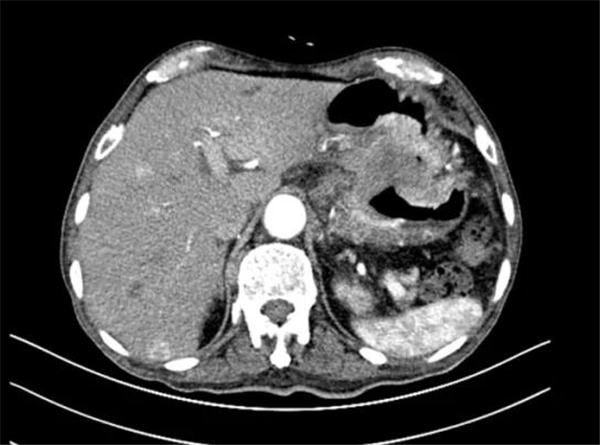

2020年12月初,燕化医院放疗科收治了一位86岁的晚期胃癌患者,老人在4年多前就明确诊断了胃癌,没有进行任何抗肿瘤治疗,今年8月患者病情逐渐加重,出现进食哽噎,进食很少,消瘦,11月份来燕化医院就医,经完善了胃镜和胸腹部CT等一系列检查后,病历记录了一长串的诊断,胃窦低分化腺癌,肝多发转移,淋巴结多发转移,贫血,低蛋白血症,胸腔积液,心包积液,电解质紊乱,肺部感染,冠心病,腹腔感染等等。

北京燕化医院放疗科夏火生主任会诊病人后,调阅了所有的CT和检验结果,发现患者长期贫血,血色素在80-90g/L之间,大便颜色发黑,便潜血阳性,说明胃癌病灶可能持续在出血,患者逐渐消瘦、虚弱跟长期慢性出血有很大关系,于是便向患者家属建议做做胃癌局部的小剂量的放疗,虽说不能治好癌症,但可以止血,如果血止住了,就相当于给老人输血了呀,而且比输血更有效,输血也就只能缓解几天,如果血止住了,不仅是改善了贫血,更重要的是降低了大出血死亡的风险,那可是质的飞跃,等老人状态恢复一些之后,也有希望能用上别的治疗手段了。

患者家属听取了夏主任的建议,于是患者从12月3日开始接受放疗。放疗2次后,患者大便颜色正常了,肉眼判断血止住了;12月14日查便常规,潜血转阴了;到12月18日,共完成了8次放疗。12月31日。患者复查血常规,血色素上升到102g/L,没再出现过黑便,患者精神和体力都有了一定的好转。